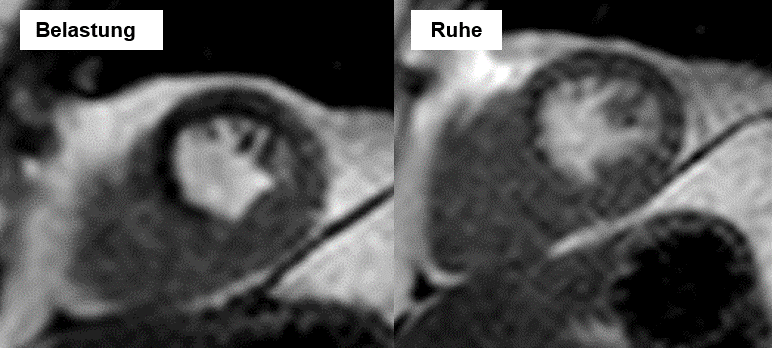

Eine der Haupt-Indikationen für die CMR ist die Ischämiediagnostik mittels Kontrastmittel-gestützter Perfusions- oder Kontraktionsuntersuchung. Bei Patienten mit mittlerer Vortest-Wahrscheinlichkeit kann hiermit mit hoher Sensitivität und Spezifität die hämodynamische Relevanz einer Koronarstenose erkannt werden. Somit ist eine Herzkatheteruntersuchung sinnvoll, wenn eine Durchblutungsstörung ohne myokardiale Narben vorliegt.

Die Belastungssituation kann sowohl medikamentös (i.d.R. durch das gut verträgliche Regadenoson, oder Dobutamin) als auch durch eine physikalische Belastung mit einem modernen MRT-Ergometer durchgeführt werden. Unser Herz-MRT-Zentrum verfügt über ein MRT-kompatibles MRT-Ergometer, mit dem wir unsere Patienten in der MRT-Röhre liegend belasten und gleichzeitig untersuchen können.

MRT-Ergometer Diagnostik der koronaren Herzerkrankung